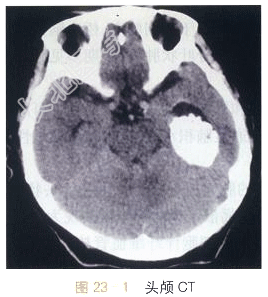

- [材料题] 女,53岁,头痛20天。影像学资料如图23-1~图23-4所示。

读片分析:头颅CT平扫显示左侧侧脑室颞角扩大,内可见不规则形高密度影;MRI检查横断面T₂WI示第三脑室内不规则形异常软组织肿块影,T₂WI等高信号,信号混杂不均,边界尚清晰;DWI呈等信号;增强扫描肿块明显强化,表面呈颗粒状。